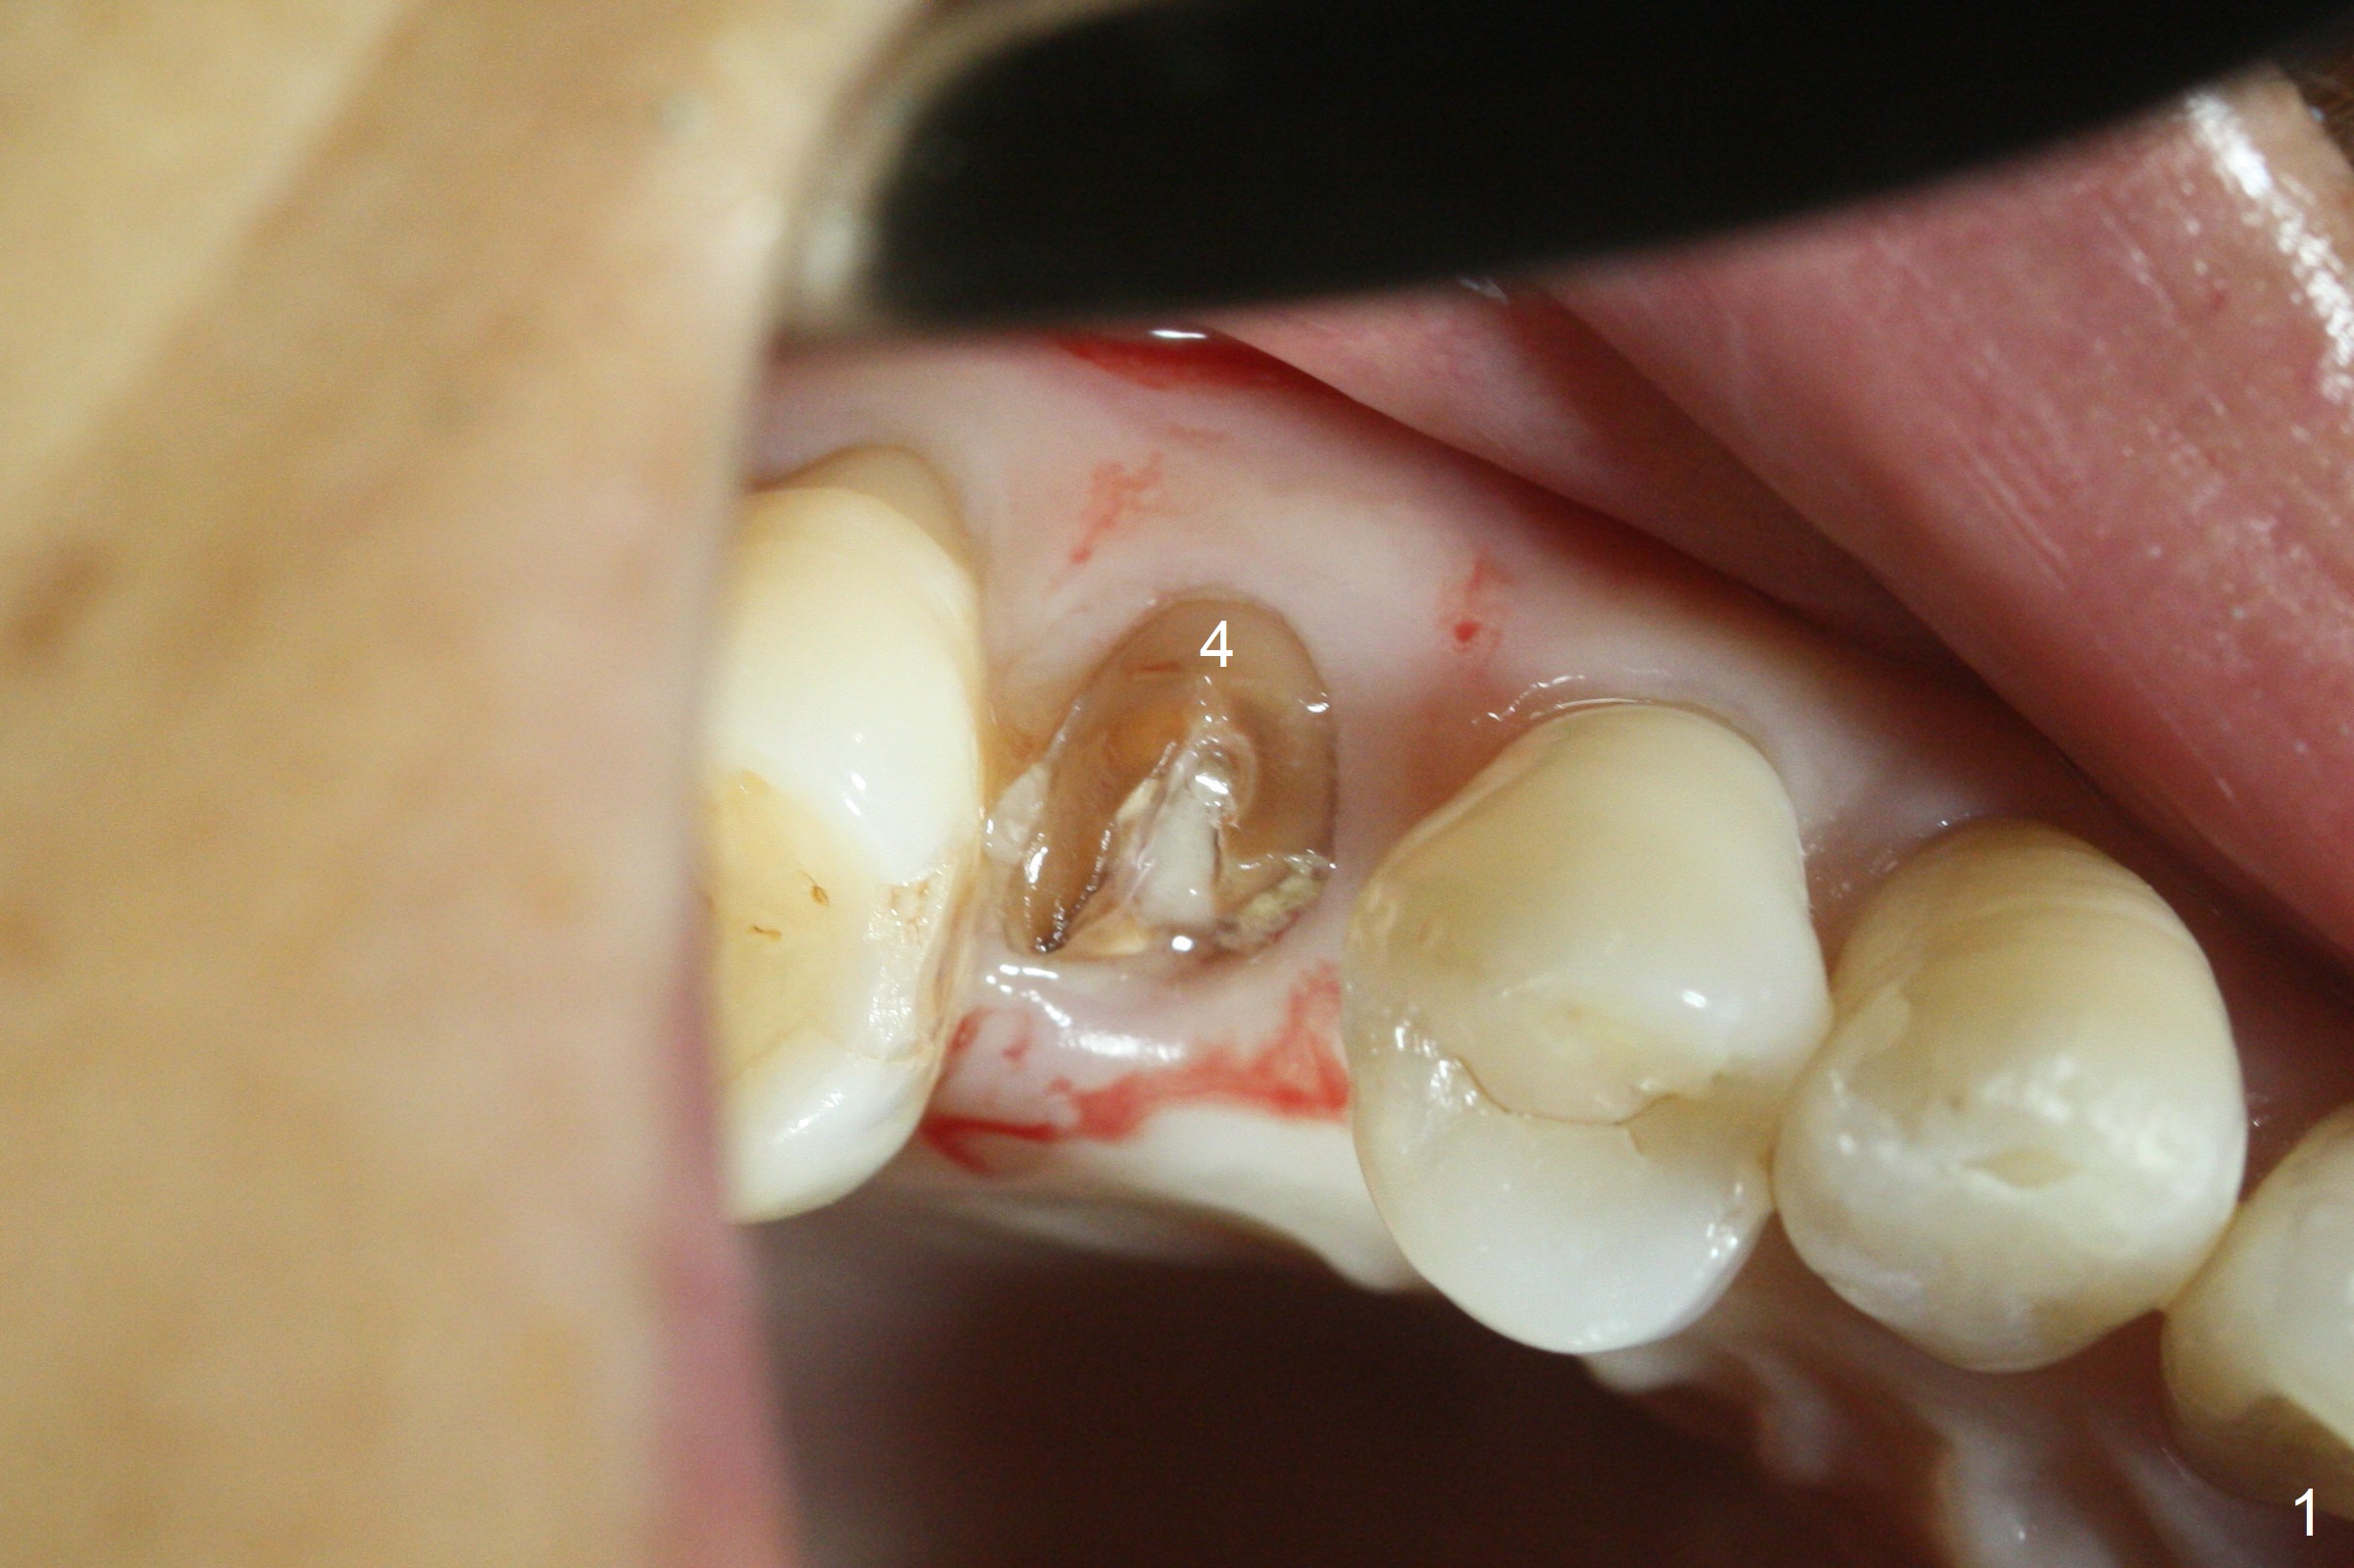

After extraction of residual root at #4 with mesiopalatal subgingival margin (Fig.1), the mesiopalatal crestal bone loss is noted. Instead of the mesial slope, the initial point of the osteotomy is at the mesial and middle (buccopalatally) of the socket bottom (Fig.2, 2'). The initial depth with 2 mm drill is 20 mm (gingival level), while the last drill (3 mm) is used for 17 mm (because of soft bone). When a 3.8x16 mm implant is placed (Fig.3,4), the distal gap of the socket is closed, suggesting that the implant moves to the least resistant area. However, it is favorable to the mesial crestal defect (Fig.4). The buccopalatal position of the abutment (4.5x4(4) mm) is a little too palatal (Fig.5, taken prior to provisional fabrication). The implant seems to have osteointegrated 6 months postop (Fig.6).